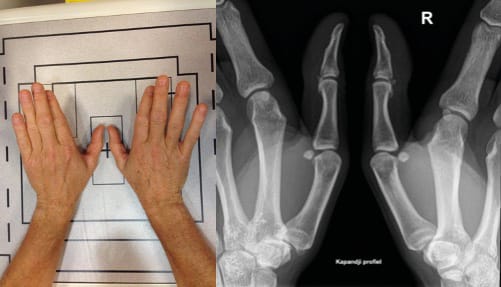

Kapandji’s frontal view equates to the Eaton view without stress, and involves placing the thumb in extension while moving the wrist into slight ulnar deviation (Figure 3). This offers good visualisation of the trapeziometacarpal joint.

Eaton’s views are the same as Kapandji’s frontal view, except that in the Eaton series the images are comparative (Figure 4), which means that a stress view (Figure 5) is taken so that the joint space can be assessed for any collapse when put under stress.

Radiological assessment of painful basal thumb arthritis will consist of Kapandji’s frontal and lateral views, an Eaton frontal view (which can replace Kapandji’s frontal view if necessary) and stress view of the TMC, a dynamic triscaphoid view and a Gedda's (Bett’s) view [12], Gedda KO (1954). Studies on Bennett’s fracture: anatomy, roentgenology and therapy. Acta Chirurgica Scandinavica, 193(Suppl): 1. [13] Taleisnik J. The Wrist, 1st edn. New York, Churchill Livingstone, 1985: 95–96. (Figure 9).